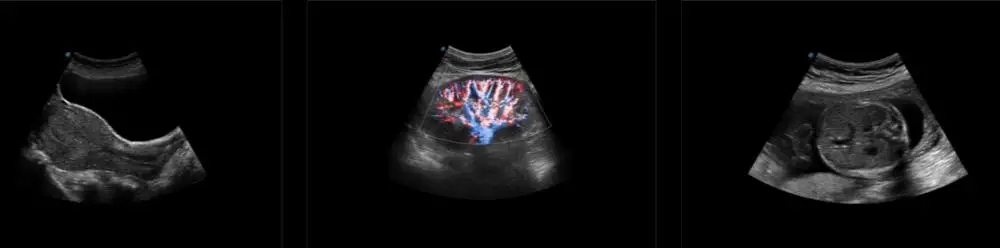

NEW Sonoscape P9 P10 P15 Doppler Trolley Ultrasound Device State of the Art Electronic Equipment